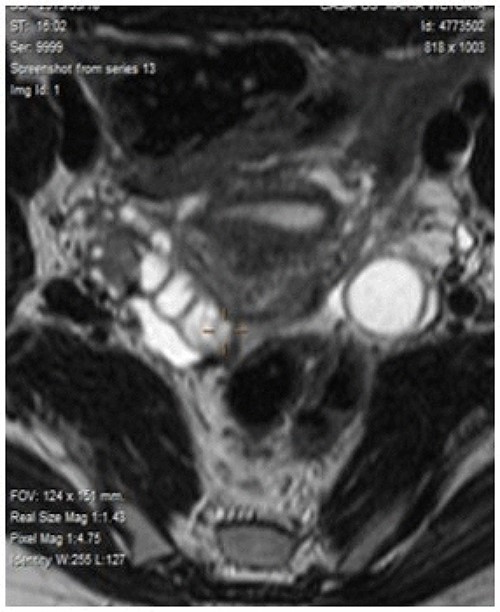

In successive controls, laboratory results revealed elevated levels of serum CEA of 28.2 ng/ml. Magnetic resonance (MR) detected adenopathy in aortoiliac bifurcation, 18 × 8 mm of undetermined origin, and a lesion in the right adnexal, 36-mm witch could correspond to a neoplasia process linked to endometrioma (Fig. 1). PET-CT scan informed adenopathy in aortoiliac bifurcation (SUV 7.3) and an image in the right adnexa with a mixed component (SUV 23) (Fig. 2).

Magnetic resonance detected adenopathy in the aortoiliac bifurcation of undetermined origin, and a lesion in the right annex, which could correspond to a neoplastic process linked to endometrioma of the right ovary or to a tubal origin.